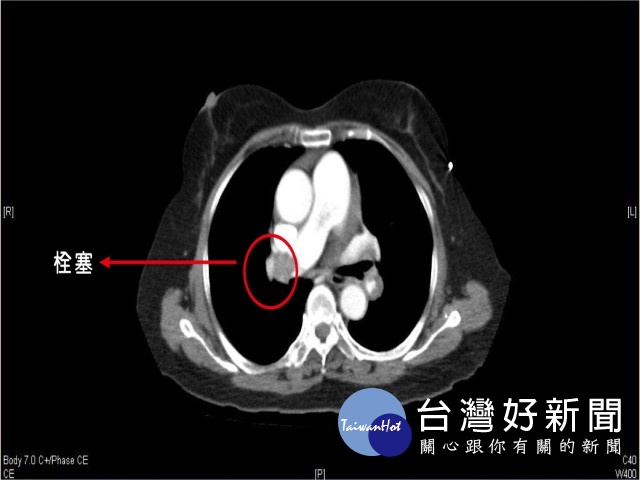

急診室醫師張勳昌從吳老血液報告中發現D-雙合蛋白(D-dimer)高出正常值10倍之多,強烈懷疑是急性肺栓塞,緊急安排胸部電腦斷層檢查,證實右邊的肺動脈有一大片血栓,緊急會診心臟內科醫師,緊急施藥治療後,轉往加護病房後續治療,各團隊合作挽回吳老一命,現健康出院,醫師仍持續追蹤中。

急診室主任張宏文表示,肺栓塞是指栓塞物質進入肺動脈或其分支,阻斷血液供應,當空有肺部呼吸帶來的氧氣,卻沒有相對的血流可將氧氣帶走,就會發生缺氧的情形,以及出現突發性的氣喘、呼吸困難急促、臉色發白、冒冷汗,胸痛、心跳加速等情形,有些病患會有咳血現象,嚴重的會出現頸靜脈怒張的情形。